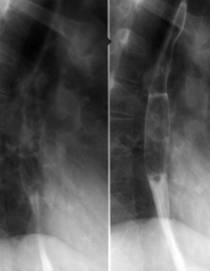

Fig. 164 Examenul esofagian normal baritat

Relieful mucos se examineaza cu pasta baritata dupa ce bolul baritat a tranzitat esofagul in pozitie verticala, incidente A-P, profil - pentru regiunea cervicala, OAS, OAD, OPS, OPD, pentru esofagul toracic. Cardia trebuie examinata atit in incidenta de fata cit si in incidenta de profil mai ales OAS.

Manevrele Valsalva si Muller sunt utilizate intrucit ele incetinesc tranzitul, cresc tonusul si destind peretele.

Explorarea trebuie completata cu examenul in decubit dorsal si Trendelenburg, pozitii ce faciliteaza o analiza mai atenta a modificarilor functionale si morfologice, facand posibila studiul peristalticei.